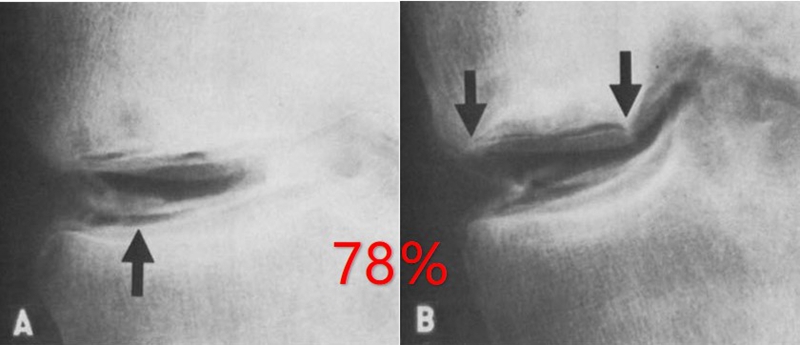

关于SONK与内侧半月板损伤,在一项研究中,关节造影检查27个SONK膝关节中发现有21个(78%)半月板撕裂,半月板碎片边缘的应力集中可能导致股骨髁缺血性坏死。

表明老年患者通过关节造影早期发现内侧半月板撕裂并及时治疗,对于避免“自发性”骨坏死的晚期变化可能很重要。